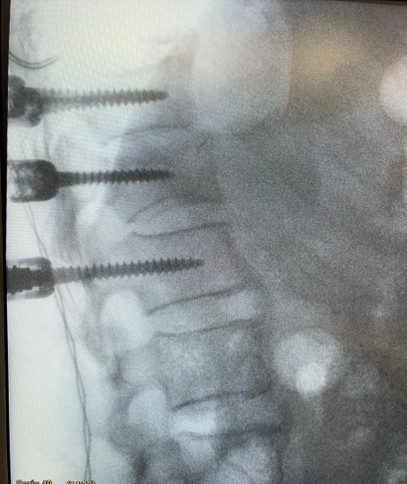

• Estabilización posterior con tornillos: Puede ser necesaria la colocación de tornillos posteriores de forma percutánea (mínimamente invasiva) o abierta. Estos tornillos pueden retirarse una vez que la fractura se considera curada (generalmente entre 8 meses y un año).

fractura de vertebras postquirurgico